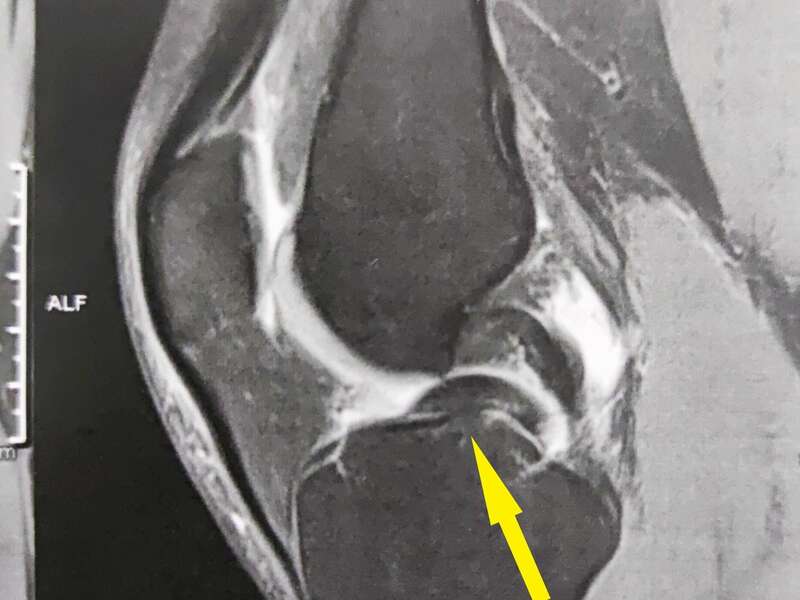

L’IRM (ou l’arthroscanner) confirmera l’existence d’une rupture ligamentaire et d’éventuelles lésions associées.

Pour évaluer la sévérité et la réductibilité d’une rupture de LCP, des radiographies en stress à 90° sont nécessaires.

La recherche de lésions associées passe aussi par la réalisation de radiographies standards du genou : fracture, arrachement des épines tibiales, contusion osseuse, lésion ostéochondrale.